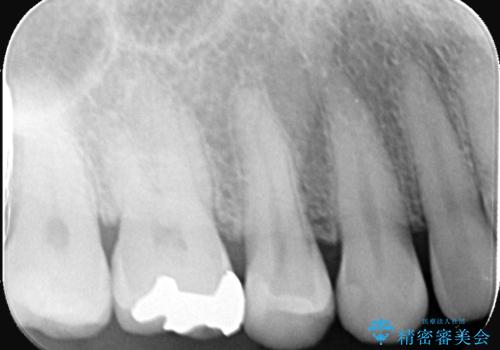

セラミックインレー 虫歯の治療

- 定期健診で虫歯が見つかり、治療が必要となりました。材料の物性を説明し、セラミックインレーでの治療となりました。

接着操作時にはラバーダム防湿を行いました。